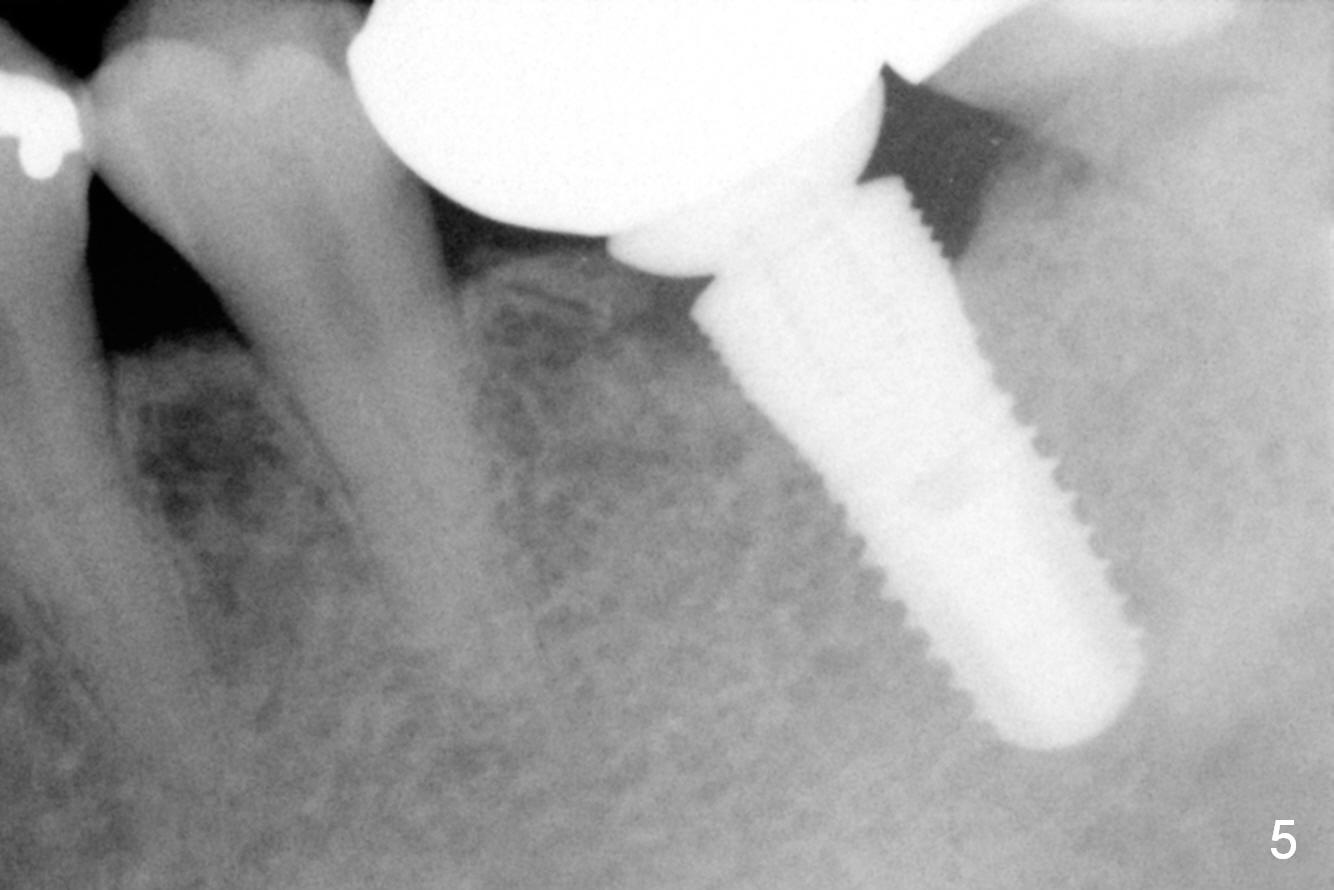

It appears that the diameter of the implant should be also controlled. A smaller implant may not lead to thread exposure and ultimately bone loss. It remains to be true 7 months post cementation (Fig.5). It appears that a 4.5 mm implant is better choice. There is no sign of periimplantitis. Oral hygiene, soft and hard tissues remains basically the same 2 years post cementation (Fig.6). The mesial open margin may be related to failure of impression material to get to the margin in spite of laser gingivectomy.